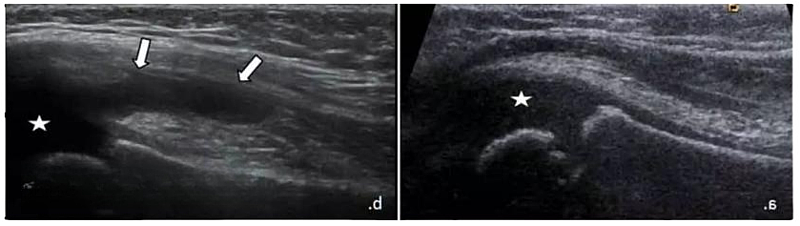

腕部较大腱鞘囊肿(*)压迫正中神经(a中空箭头,b中MN)